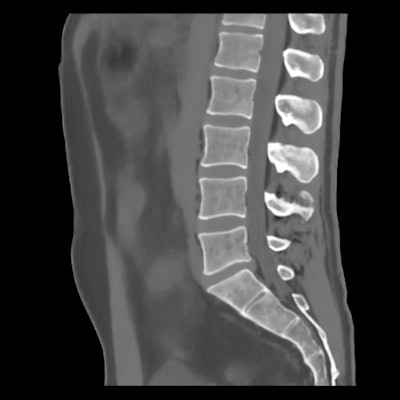

Designed to assist in diagnosis and treatment planning, BoneMRI generates a 3D CT-like image from an MRI scan to enhance visualization of bone structures, according to the company, which is a spin-off from the University of Utrecht. The software can be integrated into the radiological workflow, MRIguidance said.

BoneMRI generates 3D MRI images aimed at enhancing visualization of bone structures. Image courtesy of MRIguidance.The FDA clearance covers the use of the software in the pelvic region, including the bony anatomy of the sacrum, hip bones, and femoral heads. The company said it also intends to extend the clearance to include the spine later this year.